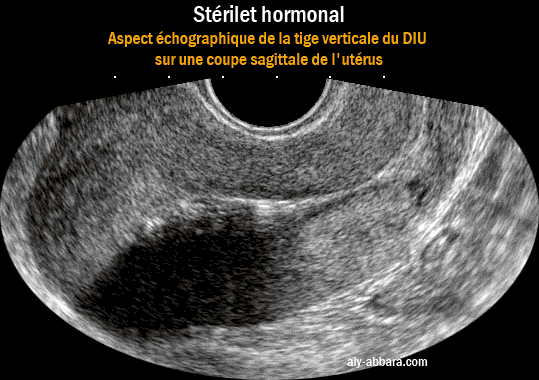

Image montrant l'un des aspects de la tige verticale du stérilet hormonal avec la formation d'un cône d'ombre lors du passage des ondes ultrsonors

Il s'agit d'un des aspects de la tige verticale du stérilet hormonal (au lévonorgestrel) avec la formation d'un cône d'ombre

par la réflexion des ondes ultrasons au niveau de cette tige.

Le cône d'ombre ne se voit pas toujours avec ce type de DIU (voir cette image)